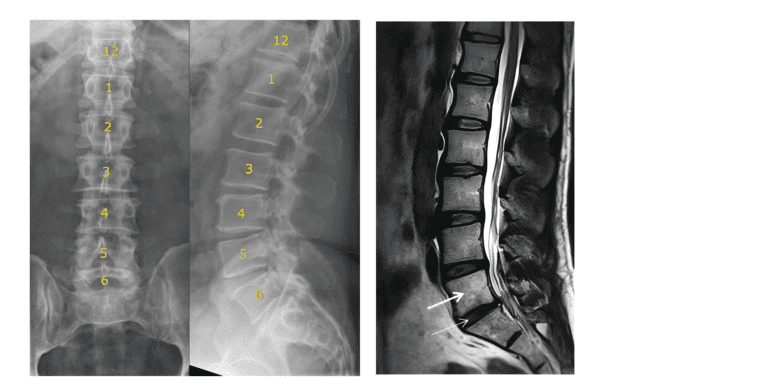

If you’ve been told you have an “extra vertebra” or a disc between S1 and S2, you may have a condition known as lumbarisation of S1.

Many people in Perth discover this finding incidentally on MRI or X-ray. Some are told it’s irrelevant. Others are told it explains everything.

Lumbarisation is a type of lumbosacral transitional vertebra (LSTV).

This anatomical variation is relatively common, with studies estimating prevalence anywhere from 4% to 30% of the population.